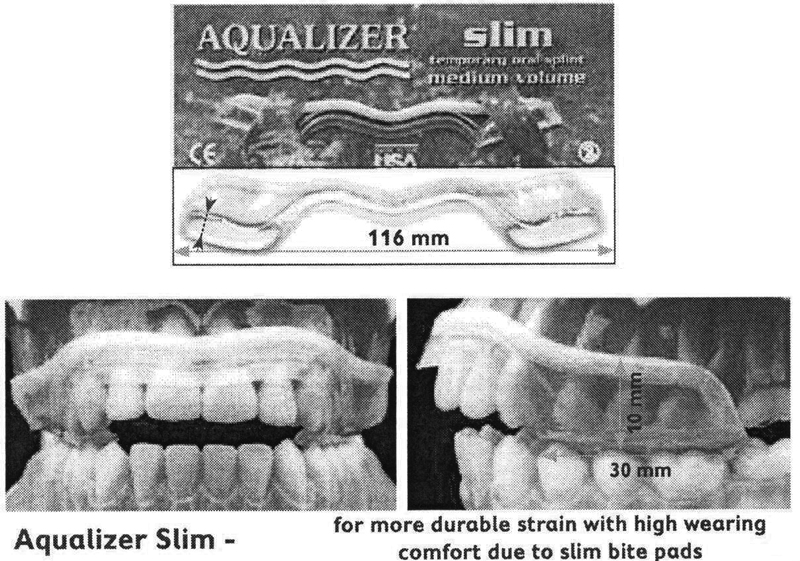

Аквалайзер дизайн СЛІМ (Aqualizer SLIM)

Аквалайзери поділяються відповідно до кількості води на High • Medium • Low . Таким чином можна регулювати висоту прикусу.

Доступні три різні різні види аквалайзерів: Aqualizer classic, Aqualizer ultra, Aqualizer ultra MINI для дітей.